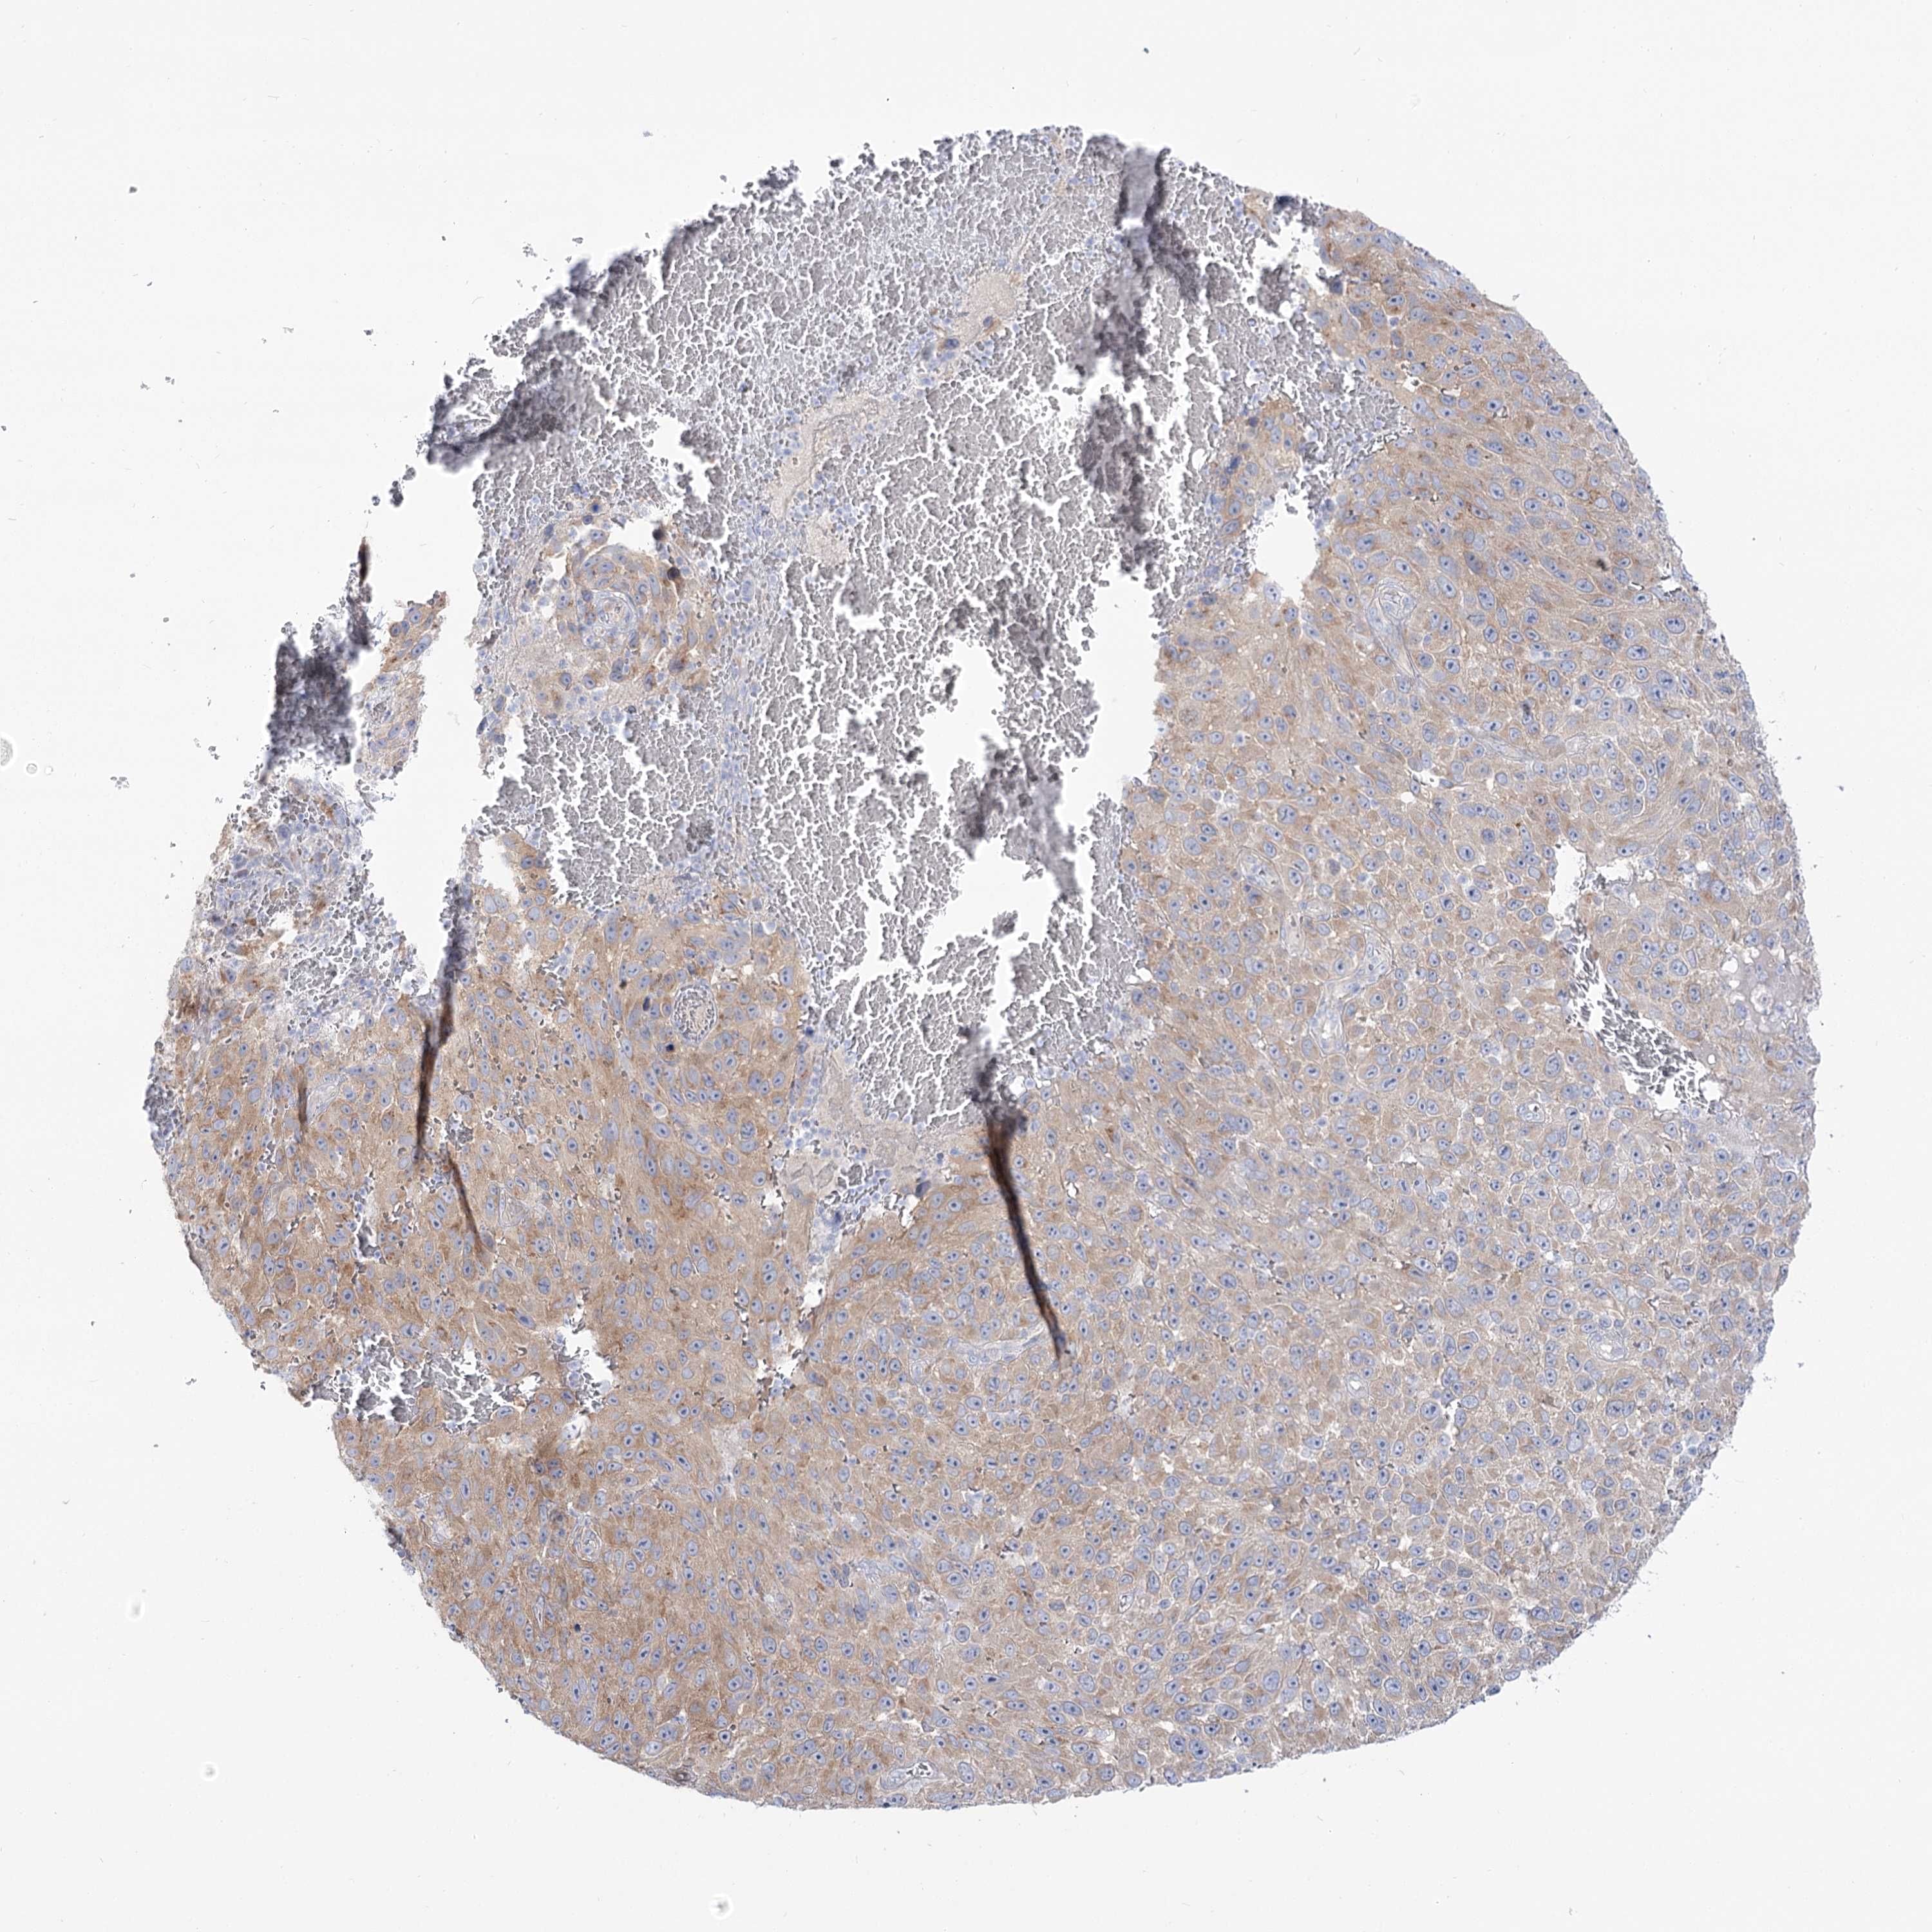

MELANOMA - Protein expressioni

A mouse-over function shows sample information and annotation data. Click on an image to view it in a full screen mode. Samples can be filtered based on level of antibody staining by selecting one or several of the following categories: high, medium, low and not detected. The assay and annotation is described here.

Note that samples used for immunohistochemistry by the Human Protein Atlas do not correspond to samples in the TCGA dataset.

Antibody stainingi

Antibody staining in the annotated cell types in the current human tissue is reported as not detected, low, medium, or high, based on conventional immunohistochemistry profiling in selected tissues. This score is based on the combination of the staining intensity and fraction of stained cells.

Each image is clickable and will lead to virtual microscopy that enables deeper exploration of all samples and also displays staining intensity scores, fraction scores and subcellular localization as well as patient and tissue information for each sample.

Antibody HPA038208

Antibody HPA038209

Malignant melanoma, NOS

Malignant melanoma, Metastatic site